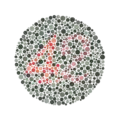

The test consists of a number of Ishihara plates, each of which depicts a solid circle of colored dots appearing randomized in color and size.[3] Within the pattern are dots which form a number or shape clearly visible to those with normal color vision, and invisible, or difficult to see, to those with a red-green color vision defect. Other plates are intentionally designed to reveal numbers only to those with a red-green color vision deficiency, and be invisible to those with normal red-green color vision. The full test consists of 38 plates, but the existence of a severe deficiency is usually apparent after only a few plates. There are also Ishihara tests consisting of 10, 14 or 24 test plates, and plates in some versions ask the viewer to trace a line rather than read a number.[4]

- Hidden digit plates: only individuals with color vision defect could recognize the figure.

Ishihara Plate No. 1 (12) Ishihara Plate No. 13 (6)

Ishihara Plate No. 23 (42) Ishihara Plate No. 29[lower-alpha 1] (a line can be traced by many of those with red-green color blindness, but not by those with normal color vision)

Ishihara Plate No. 29[lower-alpha 1] (a line can be traced by many of those with red-green color blindness, but not by those with normal color vision)